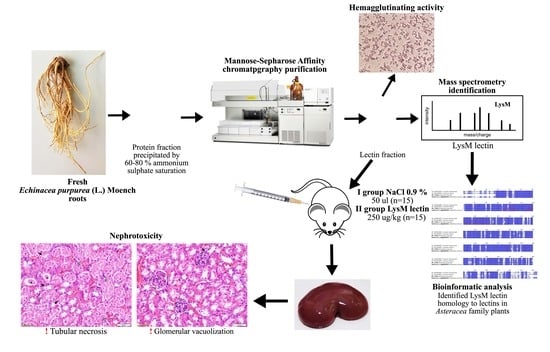

Identification of Echinacea Purpurea (L.) Moench Root LysM Lectin with Nephrotoxic Properties

2. Results

2.1. Protein Extraction, Lectin Purification, and Evaluation of Hemagglutinating Activity

2.2. Biochemical Characterisation of Purified Lectin

2.2.3. Lectin Identification

2.3. Purified LysM Lectin Impact to Kidney Morphology

4. Materials and Methods

4.1. Herbal Material Preparation

4.2. Preparation of Crude Extract and Protein Precipitation

4.3. Lectin Separation by Affinity Chromatography

4.4. Biochemical Characterisation of Purified Lectin

4.5. Evaluation of LysM Lectin Biological Activity In Vivo

4.5.2. Experimental Model